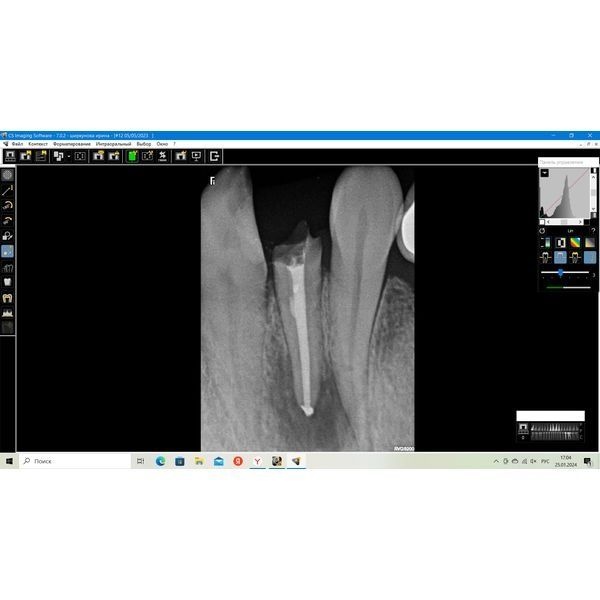

По результатам конусно-лучевой компьютерной томографии (КЛКТ):

- в канале 12-го зуба размягчён пломбировочный материал;

- у верхушки корня зуба наблюдались изменения, характерные для апикального периодонтита.

- механически распломбировали корневой канал и медикаментозно обработали его, не допустив выхода старого пломбировочного материала за верхушку корня, всё делали под контролем апекслокатора (прибора, с помощью которого определяют длину корневого канала) и прицельной рентгенографии;

- временно запломбировали корневой канал методом латеральной конденсации с помощью гуттаперчевых штифтов и силлера AH+ (т. е. сначала ввели материал в обработанный корневой канал, а затем в боковые части канала вставили дополнительные штифты, уплотняя их при помощи специальных инструментов).

Через 3 и 6 месяцев после лечения на контрольном КЛКТ было видно, что костная ткань восстанавливается.